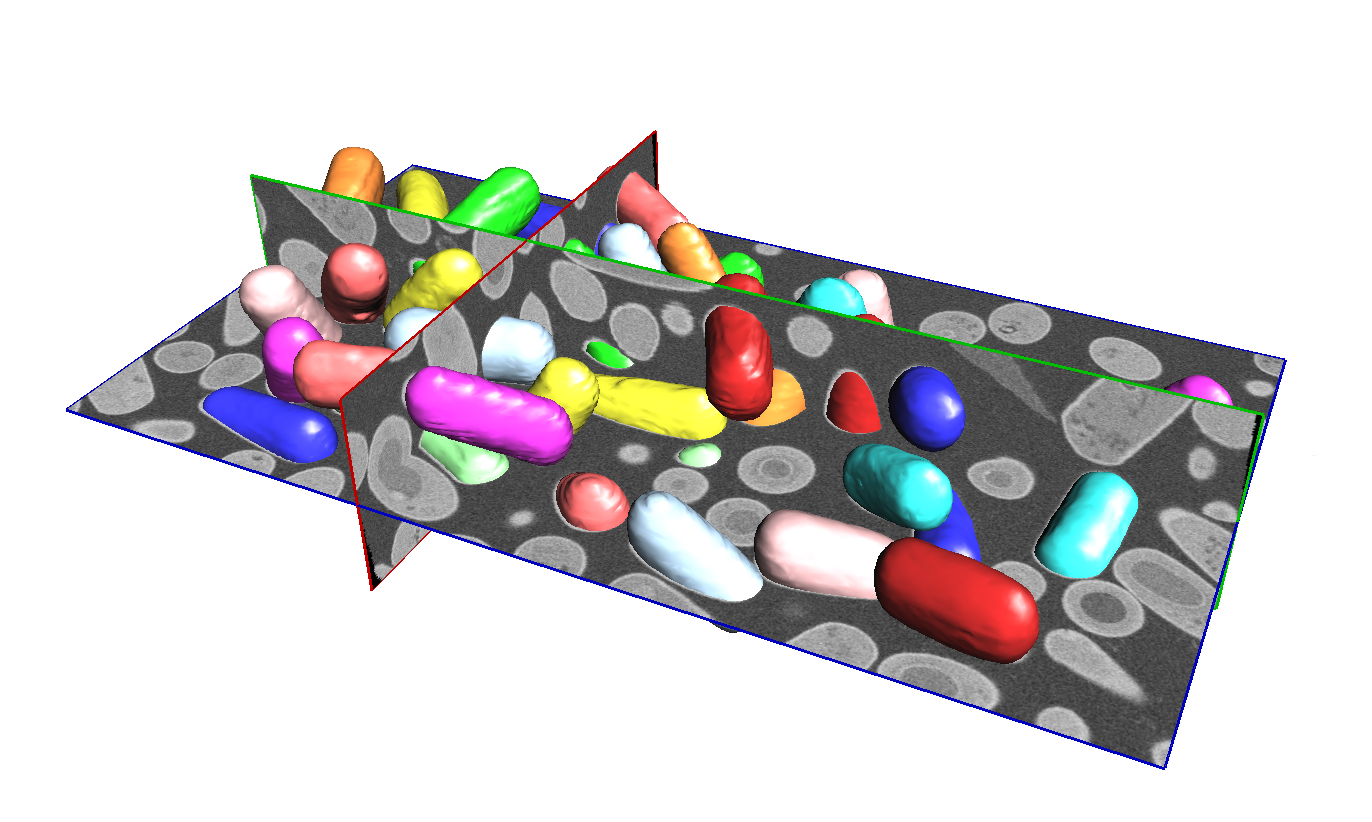

이미지 처리 기술을 이용한 의료 영상 분석은 정확한 진단 및 예측을 위해 매우 중요합니다. 이를 위해 다양한 이미지 처리 기술들이 개발되어 왔습니다. 이러한 기술들은 대개 이미지의 전처리, 분할, 분류, 추적 등의 작업에 활용됩니다.

예를 들어, CT 영상 분석에서는 엣지 검출, 분할, 특징 추출, 객체 검출 등의 작업을 수행합니다. 또한, MRI 영상 분석에서는 뇌 성분 분할, 종양 감지, 질환 진단 등에 활용됩니다. 또한, 딥러닝 기술을 이용한 의료 영상 분석은 최근에 많은 연구가 진행되고 있습니다.

의료 영상 분석을 위한 툴킷:

3D Slicer: 의료 영상 처리 및 분석을 위한 고품질 오픈소스 플랫폼입니다.

ITK-SNAP: 의료 영상 분할 및 시각화를 위한 오픈소스 소프트웨어입니다.